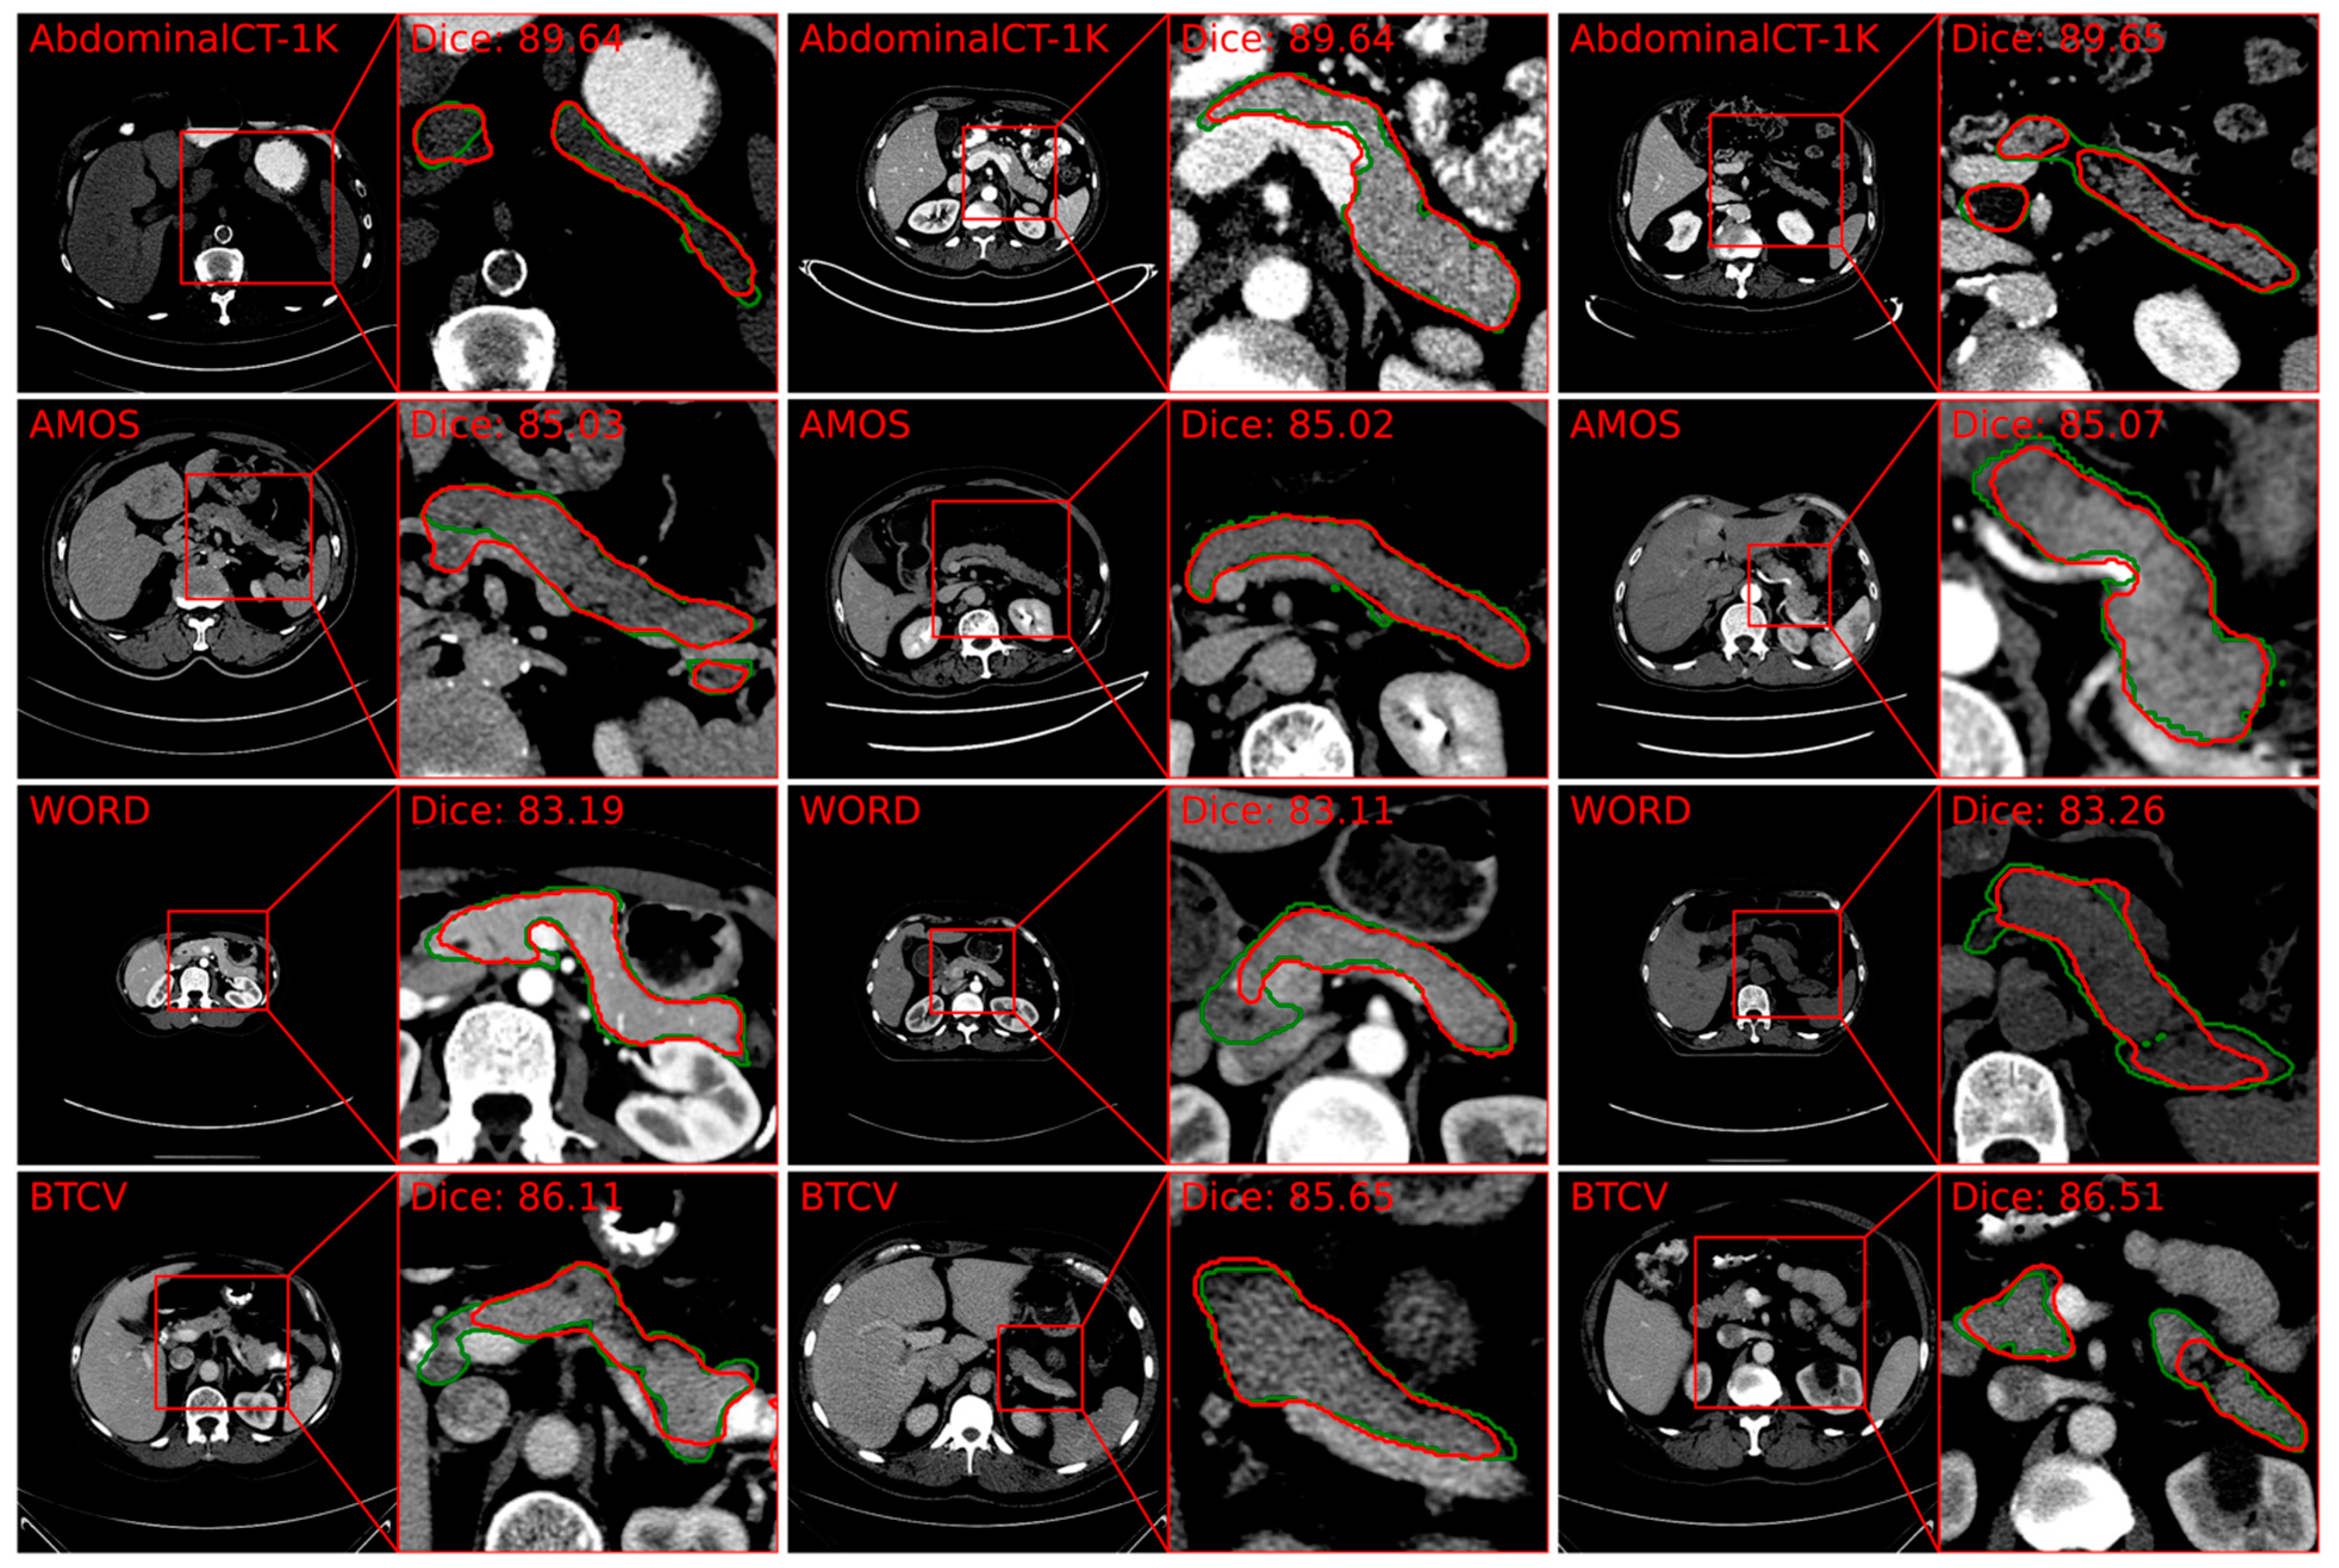

5.1.1. Segmentation of Pancreas from CT

- Zhang, Z.; Keles, E.; Durak, G.; Taktak, Y.; Susladkar, O.; Gorade, V.; Jha, D.; Ormeci, A.C.; Medetalibeyoglu, A.; Yao, L.; et al. Large-scale multi-center CT and MRI segmentation of pancreas with deep learning. Med. Image Anal. 2024, 99, 103382. [Google Scholar] [CrossRef] [PubMed]

- Ma, J.; Zhang, Y.; Gu, S.; Zhu, C.; Ge, C.; Zhang, Y.; An, X.; Wang, C.; Wang, Q.; Liu, X.; et al. AbdomenCT-1K: Is Abdominal Organ Segmentation a Solved Problem? IEEE Trans. Pattern Anal. Mach. Intell. 2021, 44, 6695–6714. [Google Scholar] [CrossRef]

- Luo, X.; Liao, W.; Xiao, J.; Chen, J.; Song, T.; Zhang, X.; Li, K.; Metaxas, D.N.; Wang, G.; Zhang, S. WORD: A large scale dataset, benchmark and clinical applicable study for abdominal organ segmentation from CT image. Med. Image Anal. 2022, 82, 102642. [Google Scholar] [CrossRef]

- Roth, H.R.; Lu, L.; Farag, A.; Shin, H.-C.; Liu, J.; Turkbey, E.; Summers, R.M. Deeporgan: Multi-level deep convolutional networks for automated pancreas segmentation. In Proceedings of the Medical Image Computing and Computer-Assisted Intervention—MICCAI 2015: 18th International Conference, Munich, Germany, 5–9 October 2015; Proceedings, Part I, 18. Springer: Berlin/Heidelberg, Germany, 2015; pp. 556–564. [Google Scholar]

- Isensee, F.; Jaeger, P.F.; Kohl, S.A.A.; Petersen, J.; Maier-Hein, K.H. nnU-Net: A self-configuring method for deep learning-based biomedical image segmentation. Nat. Methods 2020, 18, 203–211. [Google Scholar] [CrossRef]

| Zhang [88] | Linear Transformer with nnU-Net (PanSegNet) | Pancreas body | 1350 CT scans and 767 T1 and T2 (made publicly available) | 88.3% for CT, 85.0% for MRI T1, 86.3% for MRI T2. |